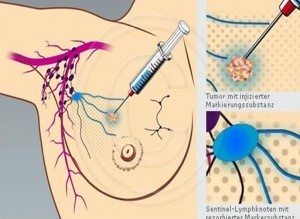

- Beim Mamma-Ca peritumoral (um den Tumor herum) und/oder subdermal (unter die Haut) in die direkte Tumorumgebung oder subareolaer (unter dem Brustwarzenhof) quadrantenorientiert.(Abb.3)

- Die hautbezogenen Applikationswege basieren auf der Annahme, dass die Milchdrüse und die darüber liegende Haut den gleichen Lymphabflussweg aufweisen.

- Hautkontaminationen sind unbedingt zu vermeiden, evtl ein Lochtuch benutzen.

- Anschließend beschleunigt eine leichte Streichmassage durch die Patientin den Lymphabfluss. Auch die Einwirkung von Wärme durch eine Wärmflasche oder ein gewärmtes Kirschkernkissen beschleunigt den Lymphabfluss.